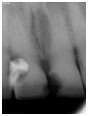

Un patient de 60 ans est venu consulter pour une mobilité d'une incisive centrale maxillaire.

Cette dent sera extraite l'implant sera posé dans la même séance et la pose de la couronne provisoire sera faite dans les 4 heures.